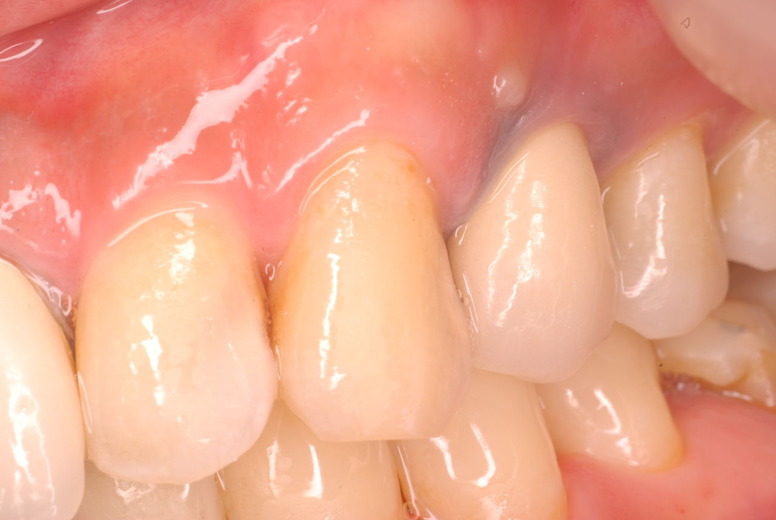

入れ歯の話から入りました。色々不満で注文があるようです。でも話が一段落して口腔内を調べると殆どの歯が重症で抜けそうな歯だらけなのです。

ご自分でやられても歯茎から血が出ないと話をされていましたが、私がブラシを当てると悲惨な状態であることがわかりました。

何故歯が悪くなるのか、歯周病で抜けるのか分からなければ何を入れても歯は悪くなり抜けていくのです。